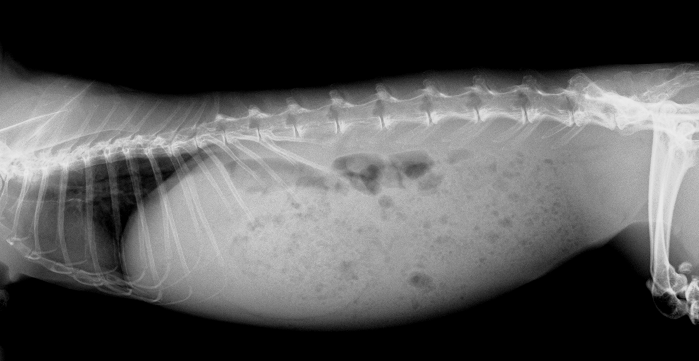

レントゲン検査

体にⅩ線を当てて骨・歯・臓器を影の画像として映し出します。短時間で撮影でき、ウサギの診断で広く使われています。ウサギでは歯牙疾患・胃腸疾患・尿石症が多いため、重要な役割を持っています。頭部のレントゲンでは歯の状態を大まかに確認することができます。臼歯の高さや均一性、歯根の過長がないかをチェックします。胸部のⅩ線検査では、心臓や肺の状態を把握できます。例えば、心臓の拡大がないか、肺腫瘍が隠れていないかをチェックします。また、偶発的に胸腺腫という大きな腫瘍が見つかることも少なくありません。症状が出ていないことも多いです。腹部のⅩ線検査では胃腸の状態、膀胱結石/尿道結石の有無、肝臓や脾臓の腫大、他の腹腔内腫瘤、女の子の場合は子宮の腫大が無いか等をチェックします。初期の腫瘍や結石は症状が出ないことの方が多いです、早期発見が重要です。